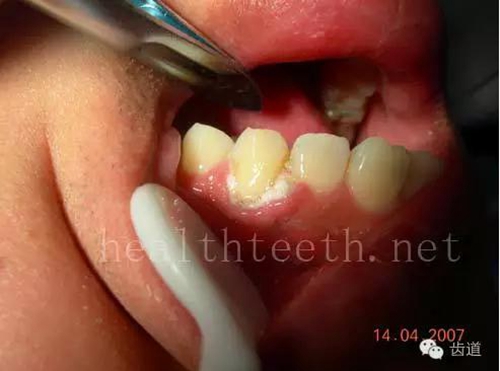

12歲孩子門牙的齲齒